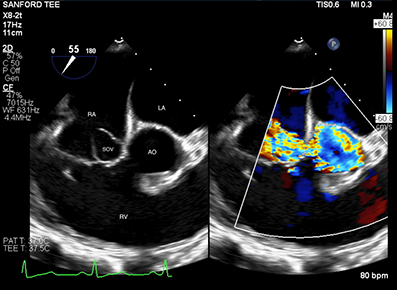

62-year-old female with hypertension and hypothyroidism presented to the ER with progressively worsening dyspnea over the past week. She also reported worsening lower extremity edema, orthopnea, and paroxysmal nocturnal dyspnea. Chest X-ray showed large pleural effusions. Her ejection fraction was 66% ejection fraction with a fistula between the right sinus of Valsalva and the right atrium on transthoracic echocardiogram (TTE) which was also seen on transesophageal echocardiogram (TEE). Her heart failure was due to the fistula as she had no coronary artery disease on coronary angiogram. She had cardiothoracic surgery for fistula repair. Postoperatively, she developed complete heart block requiring a permanent pacemaker. She had no further complications and was discharged home in good condition.

SVA affects the right sinus (94%), with the non-coronary (5%) and left sinus (1%) being less commonly involved. Aneurysm rupture typically forms a fistula into the right ventricle (60%), right atrium (29%), left atrium (6%), or left ventricle (4%), and rarely into the pericardial cavity (1%). Symptoms vary by rupture size and location. TTE is the initial diagnostic tool but has limited sensitivity (50%) for detecting fistulas, whereas TEE has a 90% sensitivity. Cardiac MRI and CT can further refine diagnoses, and cardiac catheterization assesses coronary arteries preoperatively. Surgical closure with a patch is the primary treatment for ruptured SVA, significantly improving survival rates compared to non-surgical management.